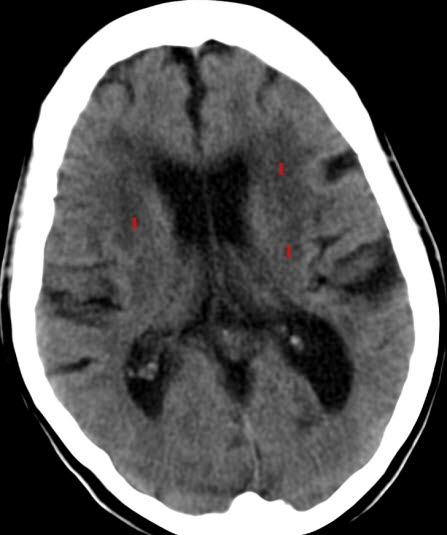

Sykehistorien og eventuelle funn ved legeundersøkelsen vil gi mistanke om at noe er galt i hjernen. CT av hjernen vil i første omgang være den avgjørende undersøkelsen for å avdekke eventuell hjerneskade eller hjernesvinn. Ved behov for mer detaljert diagnostikk kan MR av hjernen bli aktuelt. Andre tilleggsundersøkelser kan være blodprøver, nevropsykologiske tester, EEG, lumbalpunksjon, CT-PET.